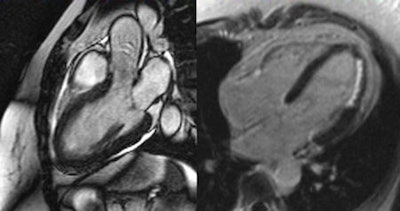

The major benefit of MRI is that it visualizes both the anatomy and the function of the heart in detail, and this makes it possible to detect conditions of the muscle as well as impaired wall motion and issues regarding oxygen supply or the pumping function. Emrich's team used cardiac MRI to examine 125 patients presenting with chest pain, elevated levels of troponin, and uncertain catheterization results. A diagnosis was established based on results from the MRI examination. A diagnosis based on the consensus of experts, including radiologists and integrating the subsequent clinical progression, served as a reference.

For 90% of these cases, cardiac MRI yielded the correct result, as was shown by a comparison with the reference diagnosis. Conditions associated with chest pain and elevated troponin levels include myocarditis, dilatative cardiomyopathy, Takotsubo cardiomyopathy, and hypertensive heart disease. In some cases, a myocardial infarction was shown that had not been detected by catheterization.